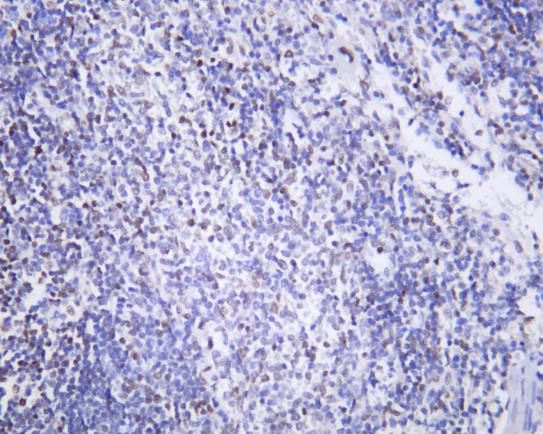

Formalin-fixed;paraffin-embedded rat spleen tissue stained for FAK (Phospho-Y397) using 13383 at 1/100 dilution in immunohistochemical analysis.